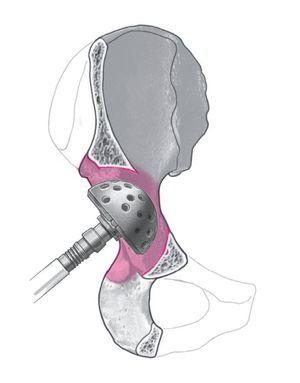

Figura 8. Fresado del centro acetabular con una fresa significativamente más pequeña que el componente retirado para obtener un nuevo centro acetabular. Para garantizar un mejor contacto de los bordes óseos con la prótesis acetabular en caso de un defecto segmentario, puede ser necesaria una medialización del centro acetabular obteniendo o aumentando un defecto acetabular central. Retirada del material fresado. Zona de contacto óseo para una fijación de tres superficies.

Figura 9. Se continúa el fresado de tamaño progresivo central sin presión hasta obtener una superficie ósea suficiente del acetábulo. Consejo: a menudo es necesario aumentar un defecto segmentario central a través de un fresado cuidadoso en profundidad con tal de obtener al final un soporte periférico suficiente a nivel del borde acetabular. En caso de defectos segmentarios se ha de tener en cuenta que se obtenga en tres zonas el suficiente contacto óseo para conseguir el anclaje press-fit (por regla general, inferior a nivel de la incisura acetabuli, anterior o anterosuperior, y posterior o posterosuperior). Para asegurar una suficiente superficie triplanar, en ocasiones es necesario debilitar el reborde preexistente para preservar el aspecto posterior.